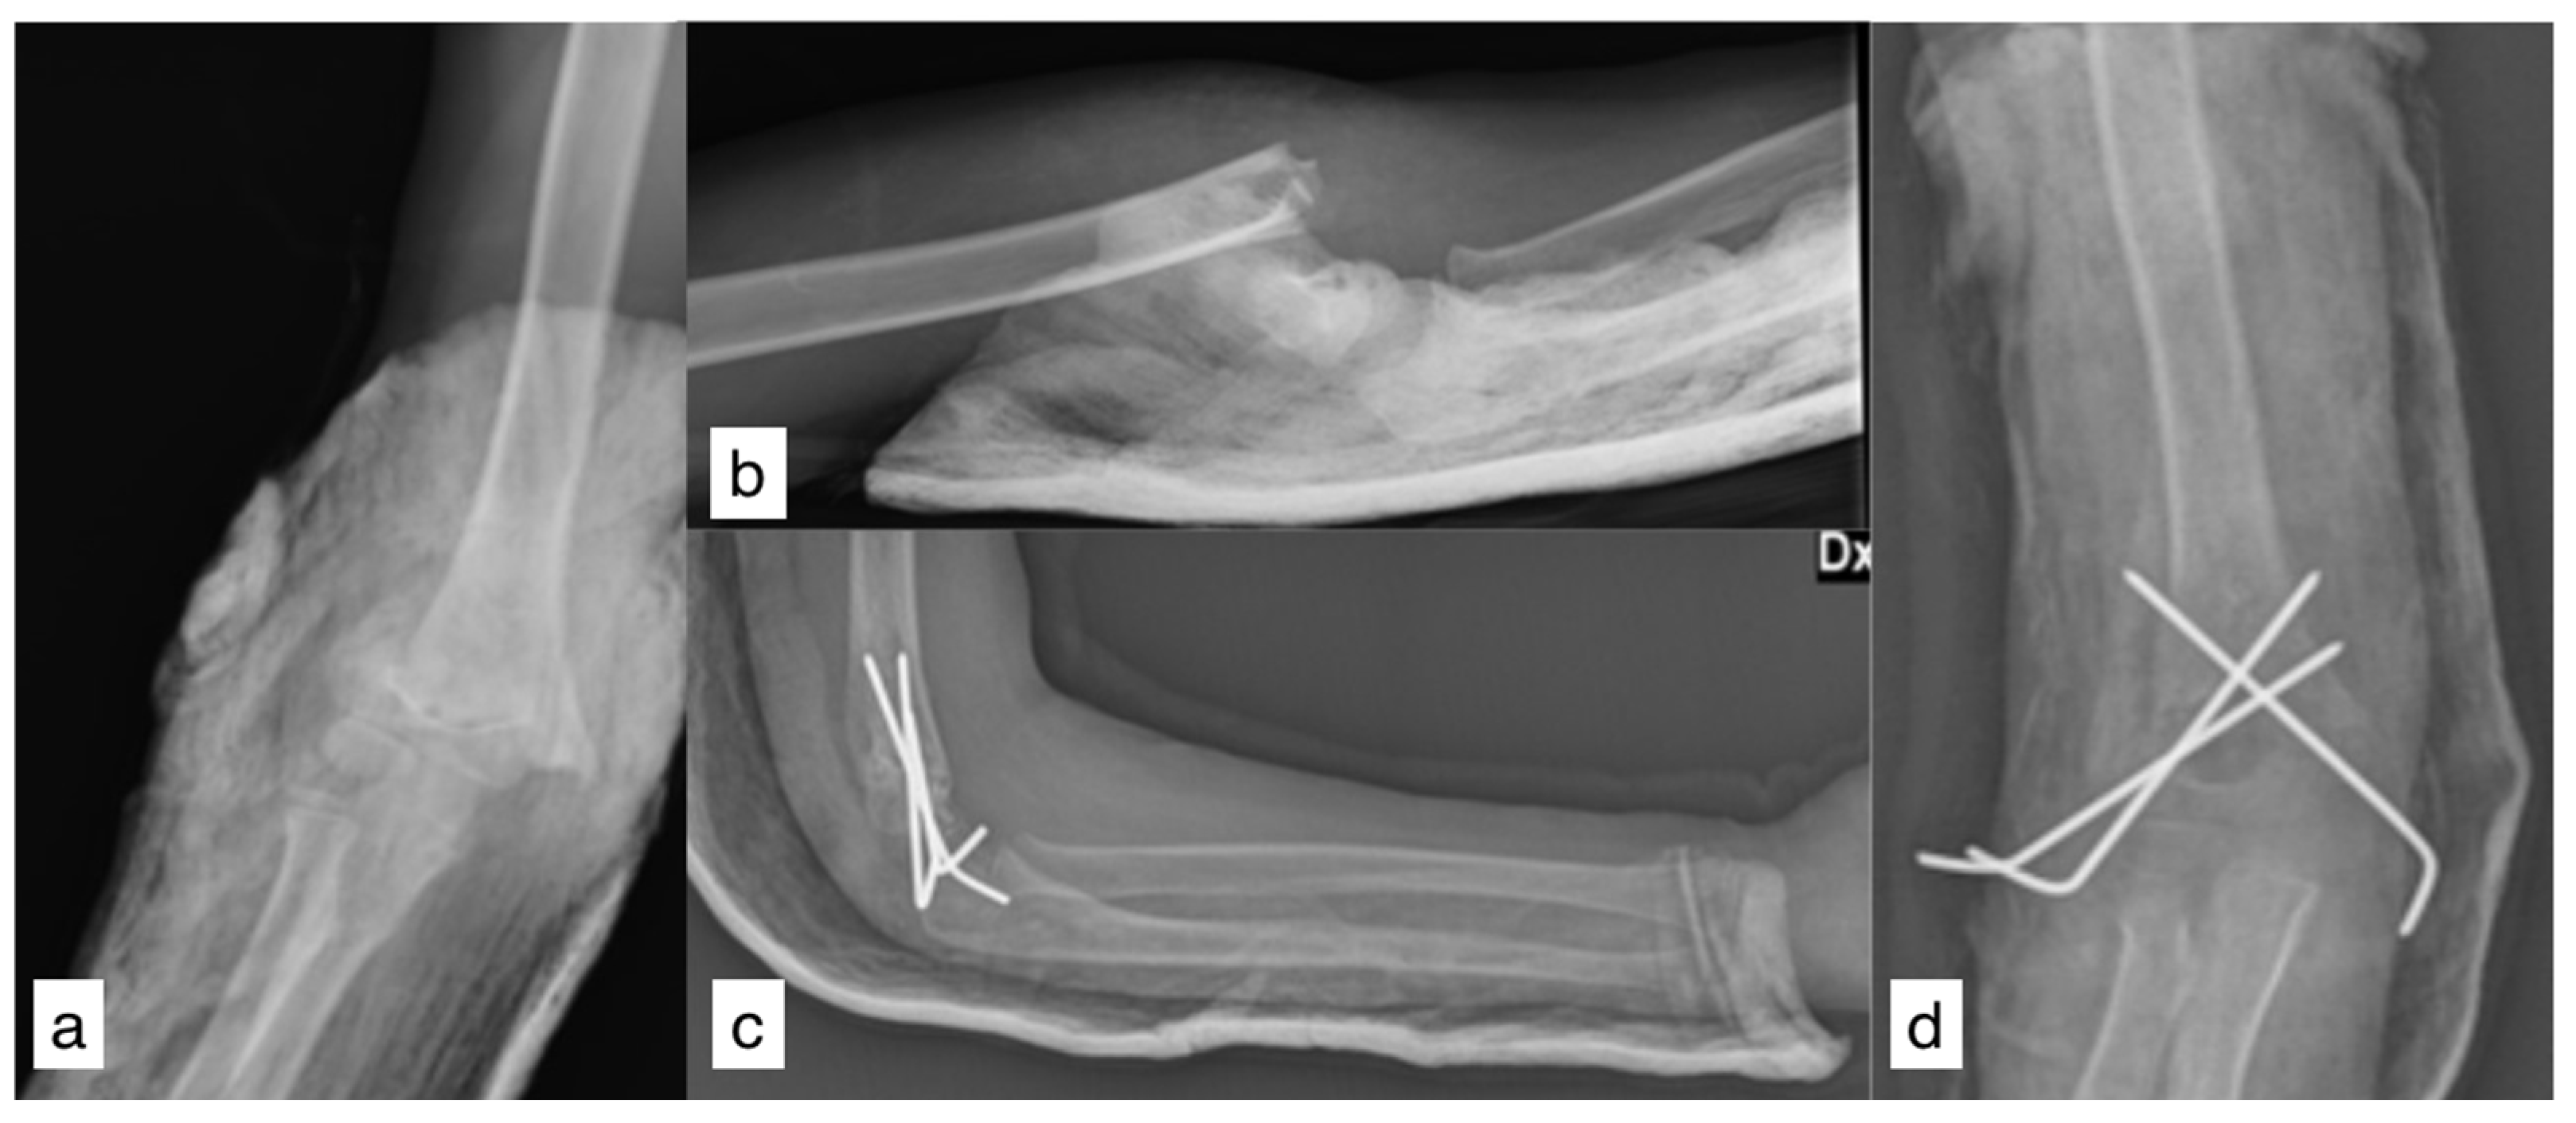

A 7-year-old right-handed female patient fell from 5 m high with an outstretched right arm. The arm was primarily swollen with gross deformities, but no neurovascular impairment was found. X-rays showed a posterolateral dislocated Gartland-type-III SCH fracture (Figure 1a,b). A mini-open reduction through lateral incision and fixation with Kirchner wires was performed in another hospital. Postoperative X-rays showed a satisfactory reduction and no inter-fragment gap (Figure 1c,d).

Figure 1.

Pre-operative X-rays (a,b); postoperative X-rays (c,d).